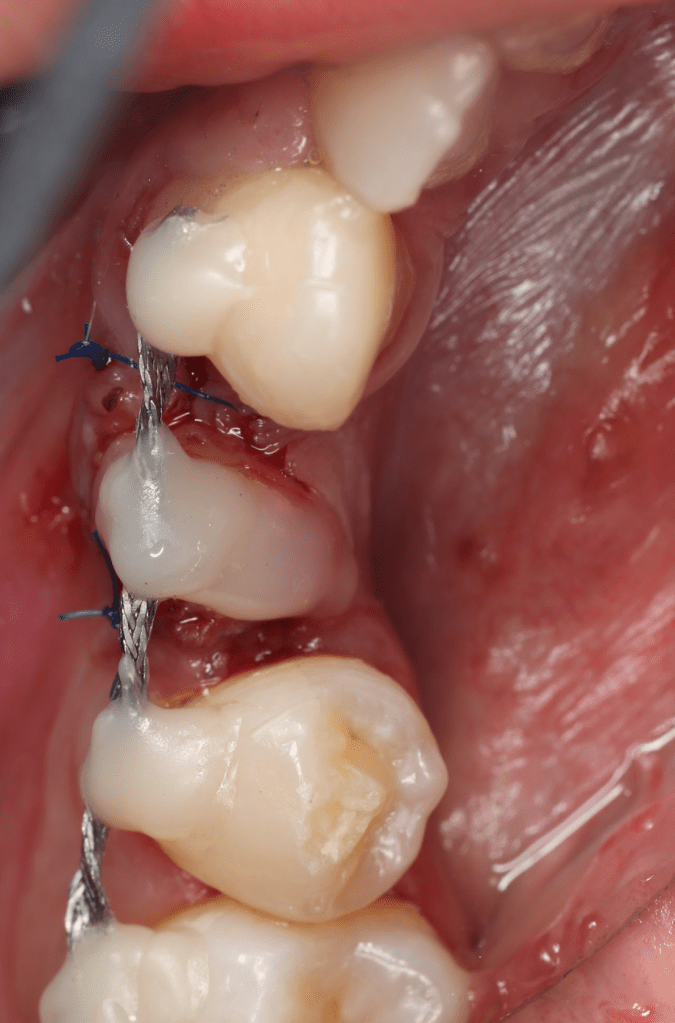

Reconstrucción preendodóntica

Reco pared vesticular